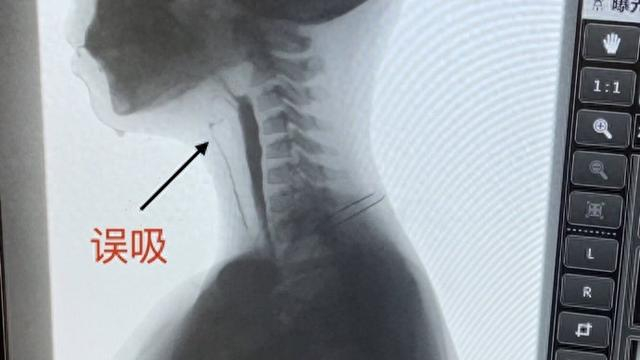

面对小喆的吞咽困难问题,复旦儿科康复科联合重症监护室、消化科、放射科、营养科组成多学科团队为其解决难题。专家在X线透视环境下,让小喆一边进食一边进行拍片,针对口腔、咽喉、食管等区域进行特殊造影,观察这些区域在进食过程中呈现出的异常状况。借助吞咽造影检查,治疗团队深入分析吞咽障碍的主要成因和具体症状,为后续治疗提供有力指导。

康复科吞咽治疗小组组长王燕娜对患儿进行了全面的临床评估和吞咽造影评估,结果显示患儿存在重度吞咽障碍,且存在误吸,需立即进行吞咽功能训练。团队制定了一套精准的康复方案,经过一个月的康复治疗,小喆的吞咽功能得到完全恢复,最终如愿以偿吃到了久违的美食。